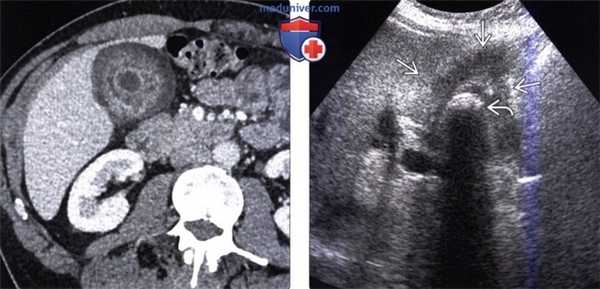

(Слева) На аксиальной КТ с контрастным усилением определяется распространенное круговое утолщение стенки желчного пузыря, которое проспективно было расценено как проявление ксантогранулематозного холецистита. Тем не менее, во время оперативного вмешательства обнаружился рак желчного пузыря.

(Справа) На сонограмме визуализируется объемное образование в ямке желчного пузыря и конкрементдающий акустическую тень. Образование не отделено от прилежащих отделов печени. На КТ (томограммы не продемонстрированы) была обнаружена локальная инвазия рака желчного пузыря в центральные отделы печени.